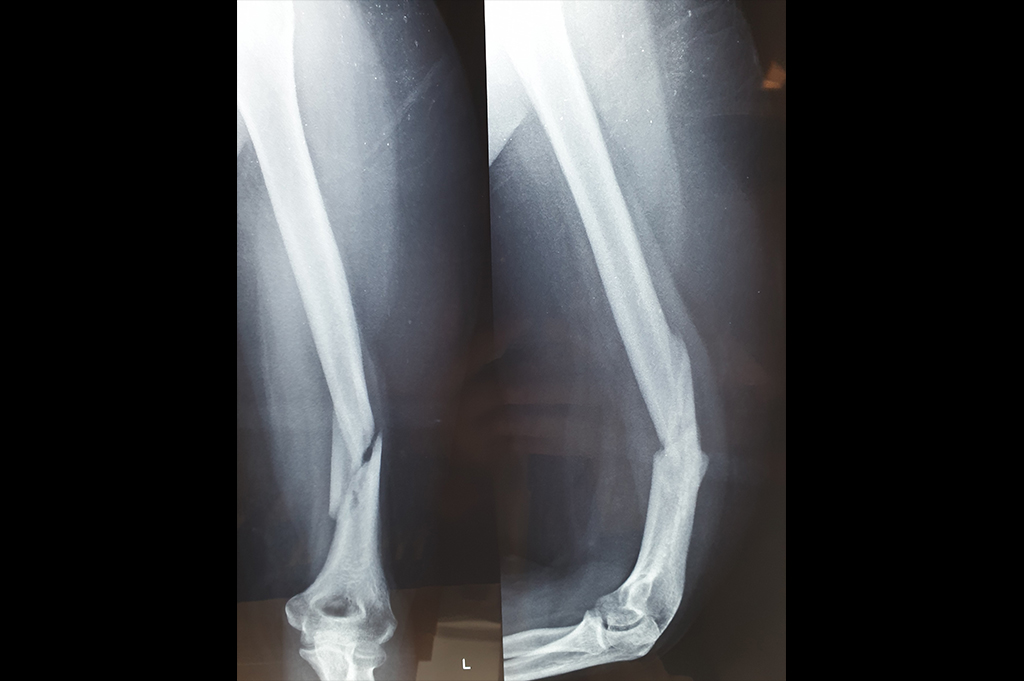

Humerus